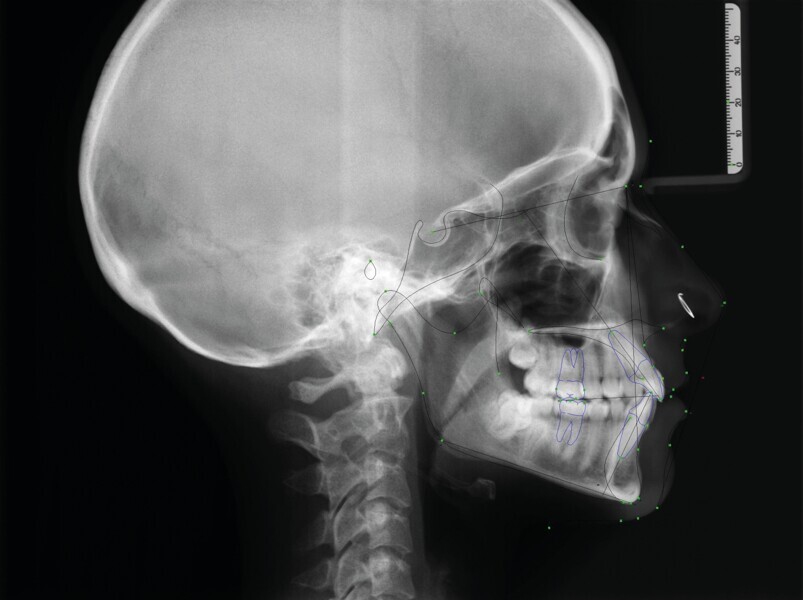

Fig. 3 : Radiographie céphalométrique initiale

L’analyse radiographique indique une structure et une morphologie normales des racines. Un vestige radiculaire est encore présent dans la zone de la dent 38 qui a été extraite (Fig. 2). L’analyse céphalométrique montre un schéma squelettique de classe I avec vestibulo-version légèrement marquée des incisives maxillaires et mandibulaires (Fig. 3).